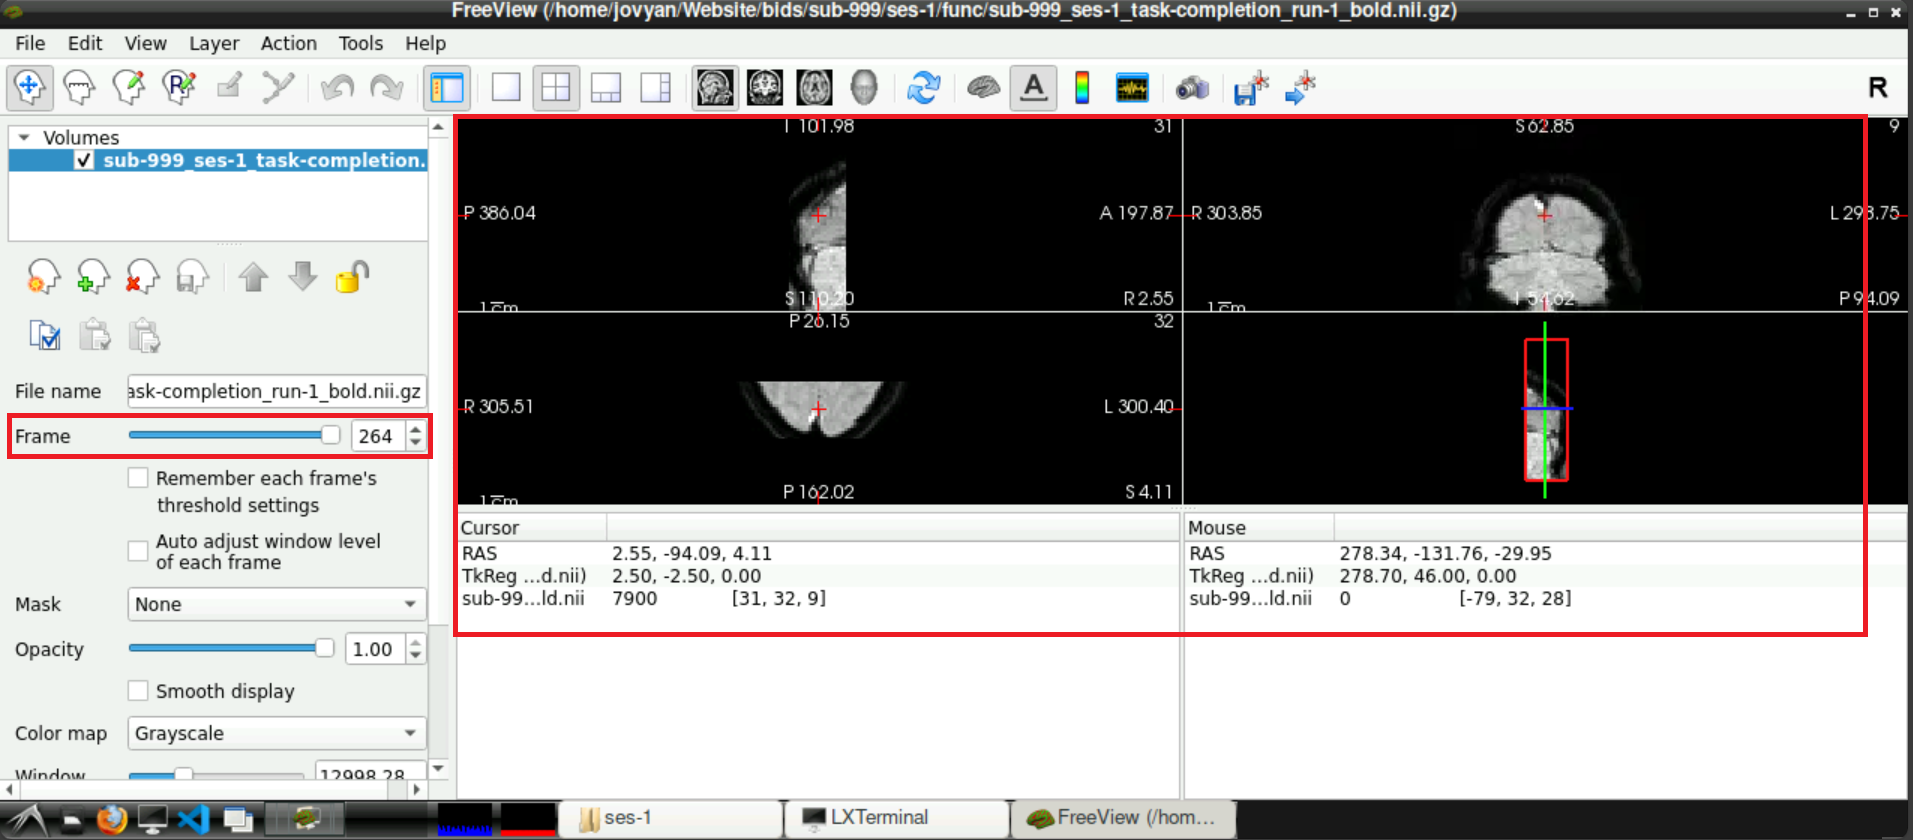

1.3 Check for Denoising Scan

To check if a denoising scan is included in you data, use the slider next to Frames (left side, roughly in the middle), to navigate to the last frame. If a denoising sequence was used during data acquisition in the scanner, this frame looks “empty”. Toggle between the last and second to last frame, to visualize the difference even more

If you confirmed the denoising being present in one of your functional runs, they will probably be there for all your runs. It might be good to check every run anyway.

3 Confirm successful removal

To confirm that the noise scan was removed from your functional scans, start freeview, load a functional scan and finally check the last frame. The original “empty” frame should now be removed and final scan should picture “normal” data.